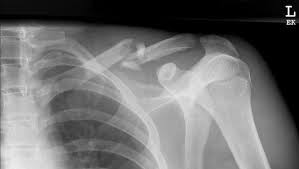

Clavicle X Ray Positioning : Shoulder Clavicle Scapula Youtube - Positioning the catheter tip too proximally, for example in the right or left brachiocephalic veins, is associated with increased risk of line infection and thrombosis.. 10 x 12 crosswise 2. In this position, the image will clearly show the condition of the. Additional imaging of the lung apices • properly positioned (not rotated or angulated): Standardized clavicle radiographs were obtained in both supine and upright positions for each patient. 10 x 12 film crosswise 2.

10 x 12 film crosswise 2. The upright position may be more comfortable than the table for some patients. Getting the most from shoulder positioning. Xray examination of the clavicle radiography of clavicle is routinely done in radiology department in both ap and ap axial projection. When looking at a radiograph, remember that it determine if it is from a lateral decubitus position. Bones • sternum • clavicles • scapulae • ribs • spine. In this position, the image will clearly show the condition of the. Boning up on humerus, clavicle, and ac joint positioning. In addition to covering anteroposterior and lateral radiographs, dr. Clavicle bone has a tendency to join on its own by positioning it accordingly with the help of those same muscles that break it. The position of the patient should be either upright or supine. Hand, thumb, fingers, wrist, forearm, elbow, humerus, shoulder and clavicle. Boning up on humerus, clavicle, and ac joint positioning.

In this position, the image will clearly show the condition of the. In addition to covering anteroposterior and lateral radiographs, dr. Ahmad explains how to work with a patient in the supine or upright position, as well. Boning up on humerus, clavicle, and ac joint positioning. The position of the patient should be either upright or supine. Getting the most from shoulder positioning. Xray examination of the clavicle radiography of clavicle is routinely done in radiology department in both ap and ap axial projection. Proper positioning for the pelvis and proximal femur the lowdown on lumbar spine positioning radiographic positioning techniques for the cervical spine boning up on humerus, clavicle, and ac joint positioning getting the most from shoulder. Digit imaging requires diligent positioning. Hand, thumb, fingers, wrist, forearm, elbow, humerus, shoulder and clavicle. Additional imaging of the lung apices • properly positioned (not rotated or angulated): Please remove all obscuring objects and, as always, practice proper radiation protection. Bones • sternum • clavicles • scapulae • ribs • spine.

Digit imaging requires diligent positioning. Please remove all obscuring objects and, as always, practice proper radiation protection. Trace the line under the clavicle towards the svc. Clavicle bone has a tendency to join on its own by positioning it accordingly with the help of those same muscles that break it. 10 x 12 crosswise 2. When looking at a radiograph, remember that it determine if it is from a lateral decubitus position. Positioning the catheter tip too proximally, for example in the right or left brachiocephalic veins, is associated with increased risk of line infection and thrombosis. Standardized clavicle radiographs were obtained in both supine and upright positions for each patient. Patient positioning techniques for a lower. The position of the patient should be either upright or supine. Boning up on humerus, clavicle, and ac joint positioning. Boning up on humerus, clavicle, and ac joint positioning. In addition to covering anteroposterior and lateral radiographs, dr.